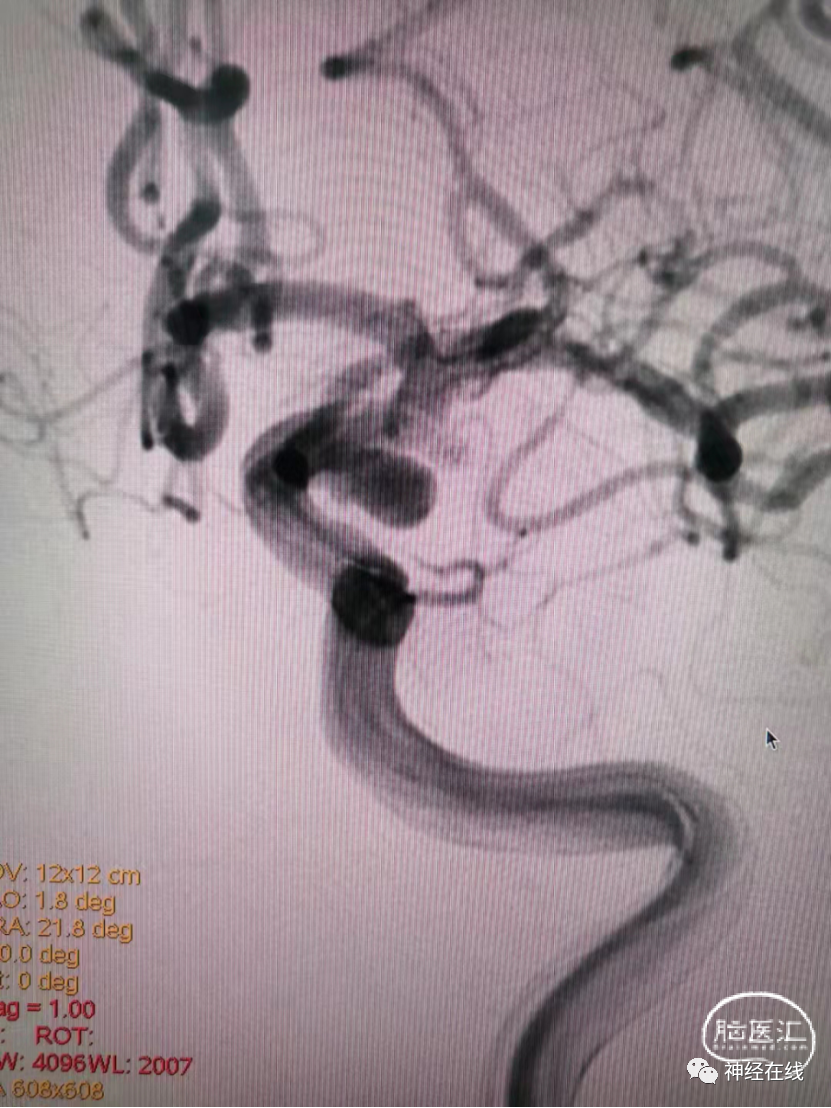

长条状破裂后交通动脉瘤弹簧圈栓塞病例